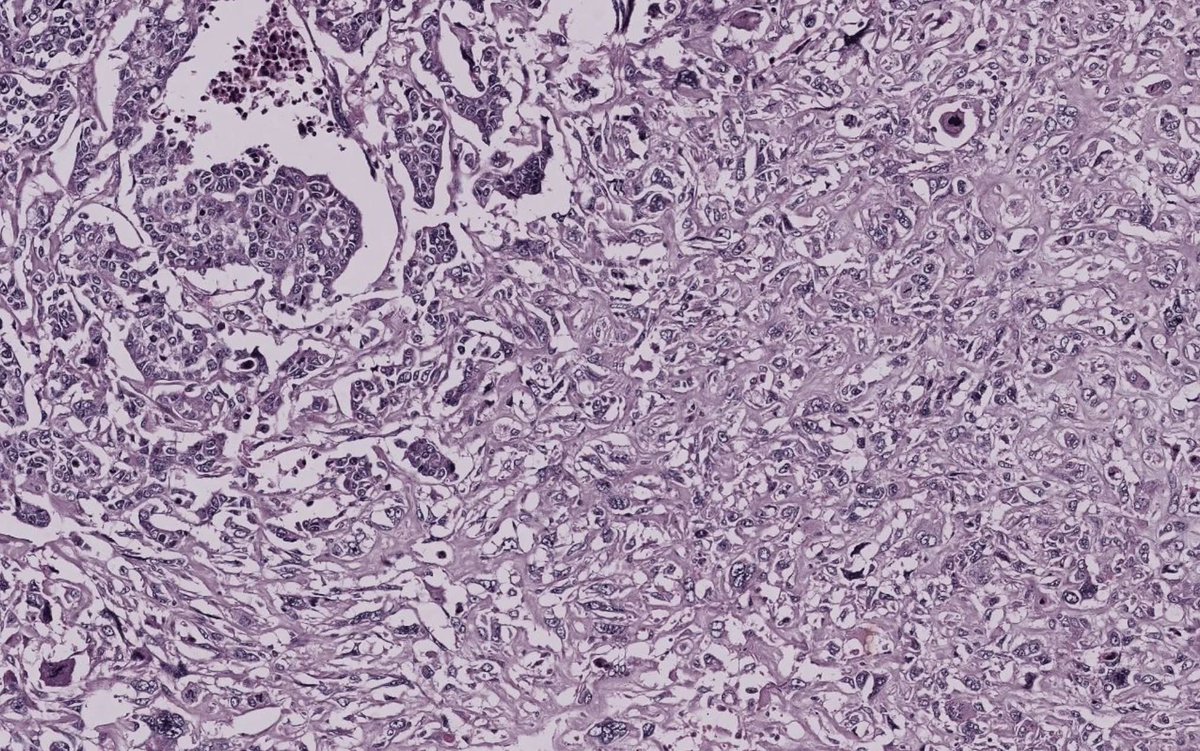

A dreadful carcinosarcoma (metaplastic carcinoma) of breast featuring poorly differentiated glands and sarcomatoid (metaplastic) component. IHC showed a triple negative carcinoma. Associated with poor prognosis. #pathology #breastpath #metaplastic_carcinoma

pathphyo's tweet image. A dreadful carcinosarcoma (metaplastic carcinoma) of breast featuring poorly differentiated glands and sarcomatoid (metaplastic) component. IHC showed a triple negative carcinoma. Associated with poor prognosis.

#pathology #breastpath #metaplastic_carcinoma